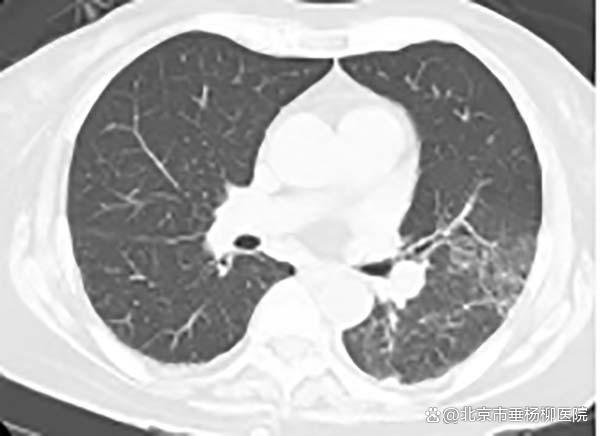

治疗效果速览

前段时间,清华大学附属垂杨柳医院重症医学科(ICU)收治了一位因骨折入院发现肺炎、呼吸衰竭的老人。经过详细问诊,得知家中卧室养有一只可爱的鹦鹉,进一步呼吸道病原学检测揭示了病因:鹦鹉热衣原体(Chlamydia psittaci,Cps)感染。科室经给予多西环素针对性抗感染治疗,老人病情得以好转。这个案例警示我们:在享受爱鸟带来的乐趣时,千万不能忽视它可能带来的传染病风险——鹦鹉热。